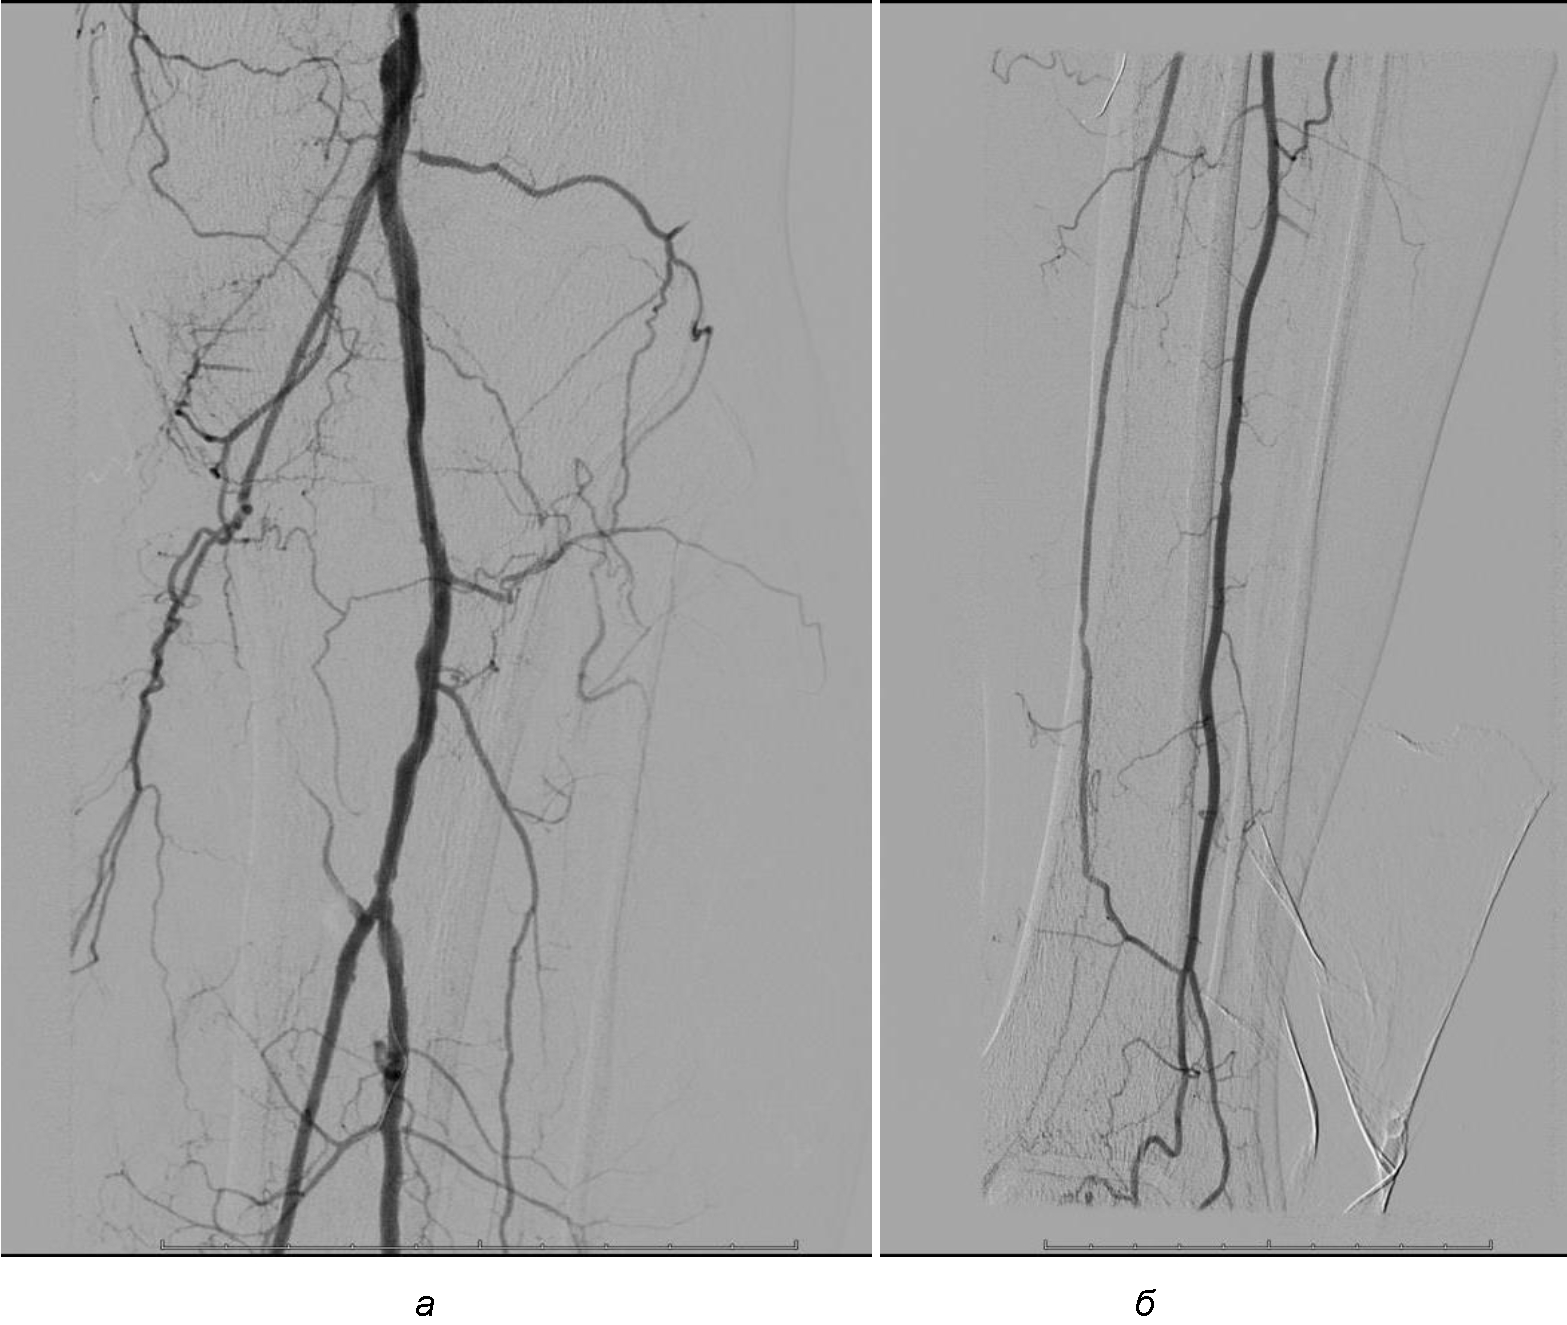

Операция. Транслюминальная баллонная ангиопластика (ТЛБАП) подколенной артерии, тибиоперонеального ствола слева. Под м/а выполнена пункция левой бедренной артерии, установлен интродьюсер 6 Fr. Выполнена селективная ангиграфия артерий левой нижней конечности при которой выявлена субокклюзия подколенной артерии и окклюзия тибиоперонеального ствола (рис. 1). Выполнена ТЛБАП в зоне субокклюзии баллоном 5,0 × 40 мм, давление 8 атм. В области тибиоперонеального ствола ТДБАП баллоном 3,0 мм × 100 мм, давление 10 атм. Получен хороший антеградный кровоток в подколенной, заднебольшеберцовой и малоберцовой артериях (рис. 2). Передняя большеберцовая артерия окклюзирована.

Рис. 2. Ангиограмма больной М. после ангиопластики. Восстановление магистрального кровотока в проксимальном (а) и дистальном (б) отделах голени